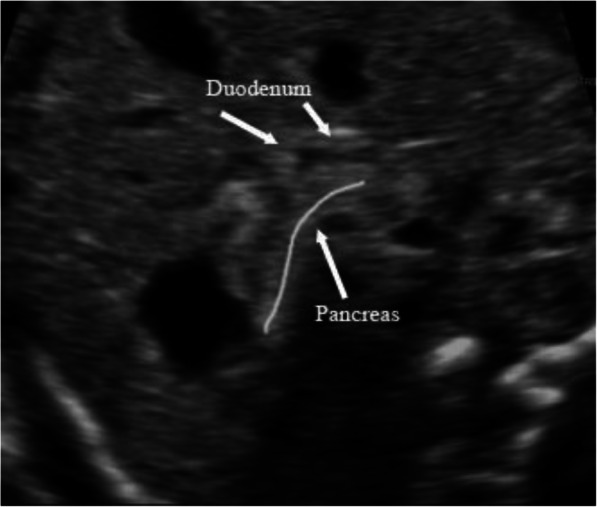

Figure 8 shows a normal duodenum and pancreas. There is no dilatation of the duodenum, and the pancreas is adjacent to the duodenum. It is clear that there is no ‘rat tail’ sign or ‘pliers’ sign.

Normal ultrasound images of duodenum and pancreas